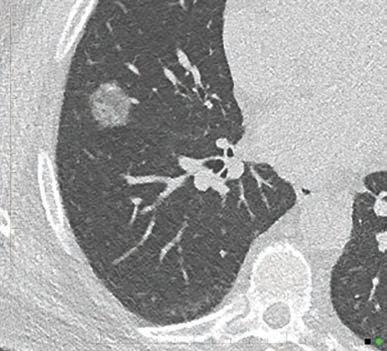

“In the future, every CT will be a photon-counting CT”

Prof. Gabriel Krestin

Erasmus Medical Center Rotterdam, Netherlands

“This will redefine our clinical decision-making right from scan one.”

Prof. Dr. med. Thomas Kröncke University Hospital Augsburg, Germany

“PCD-CT is so exciting because it provides information that existing CT detectors – the types that we’ve used for over 50 years – previously just couldn’t capture.”

Dr. Cynthia McCollough Mayo Clinic CT Clinical Innovation Center. USA

In March 2024 ChestRad introduced Photon Counting CT to Western Australia. But best not to listen to us. Find out what the experts have to say.

At Perth Radiological Clinic your chest imaging investigations are reported locally by WA’s largest team of fellowship trained accredited respiratory radiologists:

• Teaching hospital consultant radiologist appointments. Involved in multidisciplinary team meetings at FSH, MIHC, Mount Hospital, SCGH and JHC.

• RANZCR registered experts in occupational dust lung disease (RANZCR EODLD register).

• Expertise in all types of chest disease including malignancy, ILD, occupational lung diseases, lung cancer, vascular diseases and trauma.

PRC Specialist Chest Radiologist, Dr Stephen Melsom saysIf diagnosed early, particularly before symptoms develop, the progression of chest disease can be slowed

Dr Priority Line 9599 3929 perthradclinic.com.au